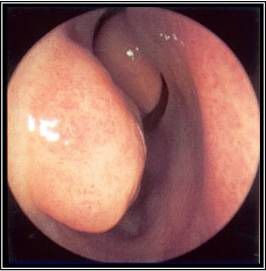

The nasal cavity should be examined for the presence of mucosal erythema or purulent discharge. Optimal exam is performed after topical decongestant spray.[18]Benninger MS, Ferguson BJ, Hadley JA, et al. Adult chronic rhinosinusitis: definitions, diagnosis, epidemiology, and pathophysiology. Otolaryngol Head Neck Surg. 2003 Sep;129(3 Suppl):S1-32. Either an otoscope or a nasal speculum and head light may be used. However, because nasal exam may be difficult or the signs nonspecific, nasal endoscopy is recommended in selected patients, including patients refractory to empiric antibiotic therapy or where there is concern for antibiotic resistance, or in immunocompromised patients.

Endoscopy can provide excellent visualization of the nasal cavity and sinus drainage paths. There are two types of endoscope: rigid and flexible. A rigid nasal endoscope has superior resolution and only requires the use of one hand. This easily allows cultures of the nasal cavity or sinus to be obtained if necessary. A flexible nasal endoscope is more comfortable for patients, but requires both hands to use. There are flexible nasal endoscopes that have a channel for collecting cultures, but these tend to be larger and more uncomfortable and they are also more difficult to reprocess. Generally, the flexible nasal endoscope is preferred in children as it is better tolerated; however, either type may be used in adults and children. Choice will depend on the practitioner's familiarity with the procedure, and most will be performed by an ear, nose, and throat specialist.

[Figure caption and citation for the preceding image starts]: Left middle meatus with severe edema and purulent secretionsFrom the collection of Melissa Pynnonen, MD [Citation ends].

[Figure caption and citation for the preceding image starts]: Nasal endoscopy of the left nasal cavity showing a small polyp and pus in the middle meatusFrom the collection of Joseph K. Han [Citation ends].